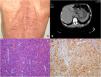

His past medical history included hypertension and neurofibromatosis type 1 (NF1). Physical examination was notable for multiple cutaneous nodules and café-au-lait spots of the skin distributed over the entire body (Fig. 1A). Upper gastrointestinal endoscopy and abdominal computed tomography scan revealed a tumor mass originating from the anterior wall of the gastric antrum with an intraluminal growth pattern (fig. 1B). The patient underwent distal subtotal gastrectomy. Histopathological examination revealed an epithelioid cell type tumor (Fig. 1C) with >10 mitoses per 50 high power fields. Immunohistochemical examinations revealed tumor cell positivity for CD117/KIT (Fig. 1D) and CD34. NF1 (von Recklinghausen disease) is an autosomal-dominant disorder occurring in one out of every 3,000 births. Gastrointestinal stromal tumors (GISTs) are mesenchymal tumors that are the most common gastrointestinal manifestation of NF1. The proximal jejunum is the most common site of GISTs in patients with NF1, and these tumors tend to be multiple. NF1-associated gastric GIST is an extremely rare event and fewer than 20 cases have been reported to date. Surgical resection with disease-free microscopic margins and an intact pseudocapsule is first-line treatment. In NF1-associated GIST, KIT and PDGFRA mutations are frequently absent and imatinib is ineffective.

(A) Image of the patient showing multiple neurofibromas and café-au-lait spots on the back. (B) Abdominal computed tomography scan documenting a 7.8 × 5.2 cm endoluminal mass in the stomach. (C) Epithelioid variant of GIST (H&E, ×100). (D) Immunohistochemistry of tumor cells (DAB, ×100) showing diffuse membranous immunoreactivity for CD117/KIT.